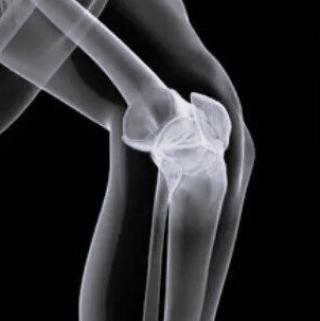

Рентген в диагностике разрыва мениска

Рентгенологическое обследование не является ключевым методом диагностики разрыва мениска, однако даёт возможность выявить анатомические аспекты костных структур коленного сустава, косвенные признаки повреждения мениска и сопутствующие дегенеративные изменения. Исследование проводится с выполнением стандартной рентгенографии колена в прямой, боковой и аксиальной проекциях, а также при необходимости в нагрузочной проекции стоя для оценки суставной щели.

На рентгенограммах коленного сустава визуализируются изменения ширины суставной щели.

Фиксируются краевые костные разрастания в области мыщелков бедренной и большеберцовой костей при хроническом процессе.

Определяется субхондральный склероз прилегающих костных пластинок.

Отмечаются околосуставные кальцификаты при застарелых травмах или хроническом синовите.

Фиксируется изменение конгруэнтности суставных поверхностей при сочетанных повреждениях.

При выраженном суставном выпоте визуализируется повышение плотности мягкотканевых структур параартикулярной области.

В дифференциальной диагностике рентгенография позволяет исключить переломы, остеоартрит, остеохондропатию и опухолевые процессы.